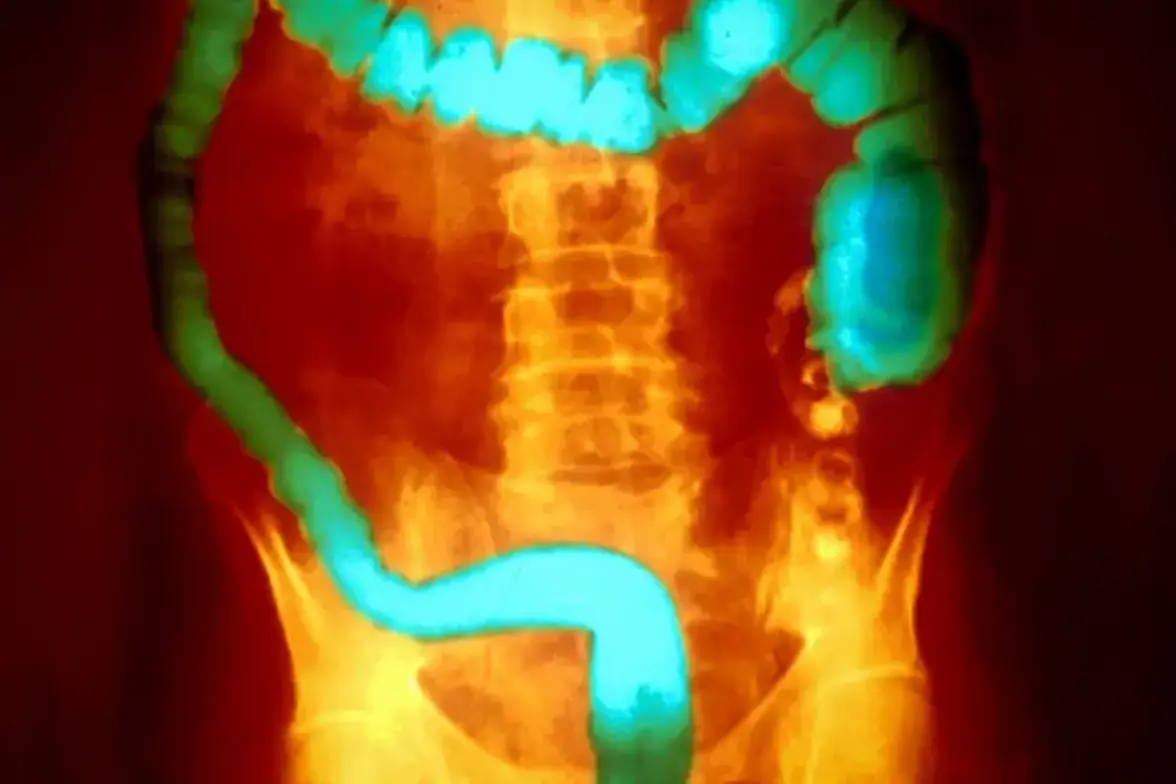

Кишечный эпителий содержит одну из самых больших популяций макрофагов, обитающих в тканях, которые служат первой линией защиты от патогенных микроорганизмов, проникающих из просвета кишечника. Авторы недавнего исследования, опубликованного в журнале Science, предположили, что количество макрофагов, обитающих в кишечнике, при ЯК снижается, что приводит к нарушению целостности эпителия, и поэтому исследовали макрофаги в тканях толстой кишки при ЯК. Ученые обнаружили, что в тканях толстой кишки, полученных от пациентов с ЯК, количество макрофагов, обитающих в тканях, было снижено в областях, где не было признаков воспаления и предположили, что потеря макрофагов предшествовала явному воспалению. На мышиных моделях химическая или генетическая абляция макрофагов повышала восприимчивость к повреждениям кишечника.

Чтобы выявить потенциальные факторы, которые могут нарушить функцию макрофагов, ученные исследовали бактерии, присутствующие в образцах кала пациентов с ЯК. Они идентифицировали бактерии, продуцирующие токсины, принадлежащую к роду Aeromonas, обозначенные как Aeromonas sp. MTB (macrophage-toxic bacteria), которые экспрессируют фактор вирулентности аэролизин. Макрофаги проявляют более высокую чувствительность к гибели клеток, вызванной аэролизином, чем эпителиальные клетки, что, как предположили исследователи, может привести к нарушению защитного барьера без прямого повреждения эпителия.

МТВ устойчиво колонизировали мышей в патологических условиях, истощая макрофаги и повышая чувствительность к кишечным раздражителям. МТВ способствовали развитию колита у мышей, получавших декстрансульфат натрия, или у мышей, у которых отсутствовала экспрессия интерлейкина-10, с фенотипами, напоминающими ЯК, но не у безмикробных мышей. Мутант MTB с дефицитом аэролизина не вызывал колита, что подтверждает роль этого токсина. У мышей предварительная обработка поликлональными антителами к аэролизину предотвращала МТВ-индуцированный колит, а моноклональные антиаэролизины улучшал течение заболевания.